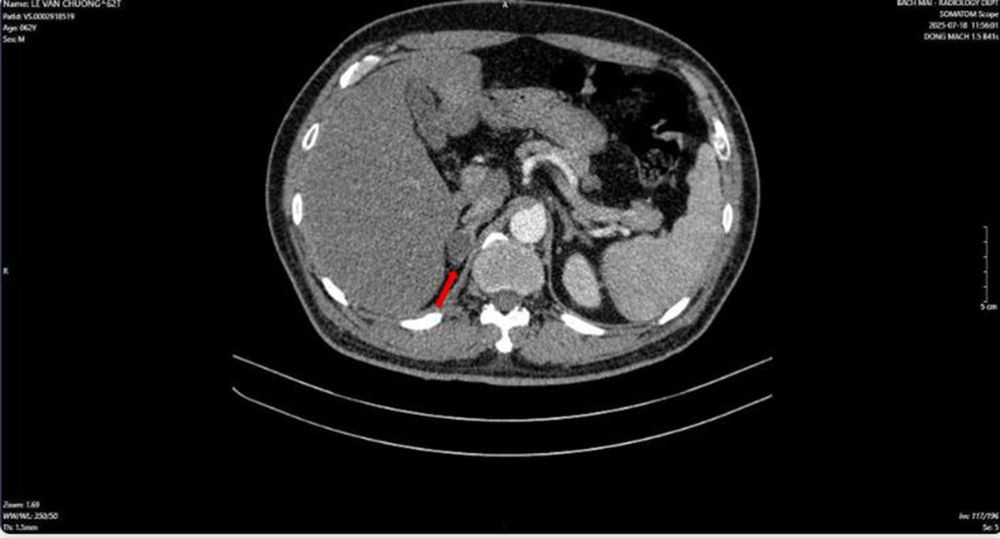

Hình ảnh dày tuyến thượng thận phải tạo nốt có kích thước 19 x 17 mm (Ảnh: BV Bạch Mai)

Kết quả sinh thiết và phân tích mô bệnh học, kết hợp hóa mô miễn dịch, đã làm rõ bản chất bệnh lý: khối u tại phổi là ung thư biểu mô tuyến của phổi; trong khi đó, khối u tại tuyến tiền liệt là ung thư biểu mô tuyến với điểm Gleason 9 – thuộc nhóm nguy cơ cao. Đáng chú ý, hai loại ung thư này có nguồn gốc độc lập, không phải là hiện tượng di căn chéo.